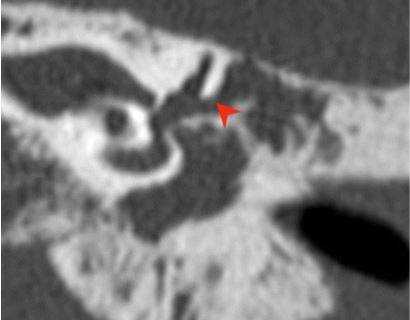

Шваннома лицевого нерва: осевое КТ-изображение (костное окно) демонстрирует расширение ганглия, присутствует однородная масса мягких тканей (стрелка)

Хроническое воспаление среднего уха с холестеатомой: коронарная КТ показывает боковой свищ полукруглого канала (стрелка), вызванный эрозией кости из-за роста новообразования